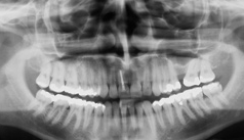

Die Patientin war zwölf Jahre alt. Auf dem OPG (Abb. 10) war die unterschiedliche Lage bei-der Oberkiefereckzähne in ver­tikaler Richtung zu erkennen. Bei der klinischen Untersuchung war vestibulär im Bereich des Eckzahnes 23 eine leichte Auftreibung zu palpieren. Die chirurgische Freilegung und aktive Eruption wurde zu die-sem Zeitpunkt nicht veranlasst, da die vertikale Verlagerung und die ausreichenden Platzverhältnisse einen eventuell spontanen Durchbruch erwarten ließen.

Ein Jahr später zeigt das neuangefertigte OPG (Abb. 11) die unveränderte Position von 23. Die klinische Situation zum gleichen Zeitpunkt zeigen die Abbildungen 12a–d. Der Zahn wurde gemäß der geschlossenen Elongation chirurgisch für die kieferorthopädische Einstellung vorbereitet. Die Einstellung des verlagerten Eckzahnes erfolgte nach dem vorher beschriebenen Konzept (Abb. 13a, b). Die Zähne 16 und 26 wurden mit Bändern und einem Palatal Bar mit Ausleger als Verankerungseinheit versehen. Die Gestaltung des Auslegers erfolgte so, dass der Zahn 24 gehalten wurde (Abb. 14).